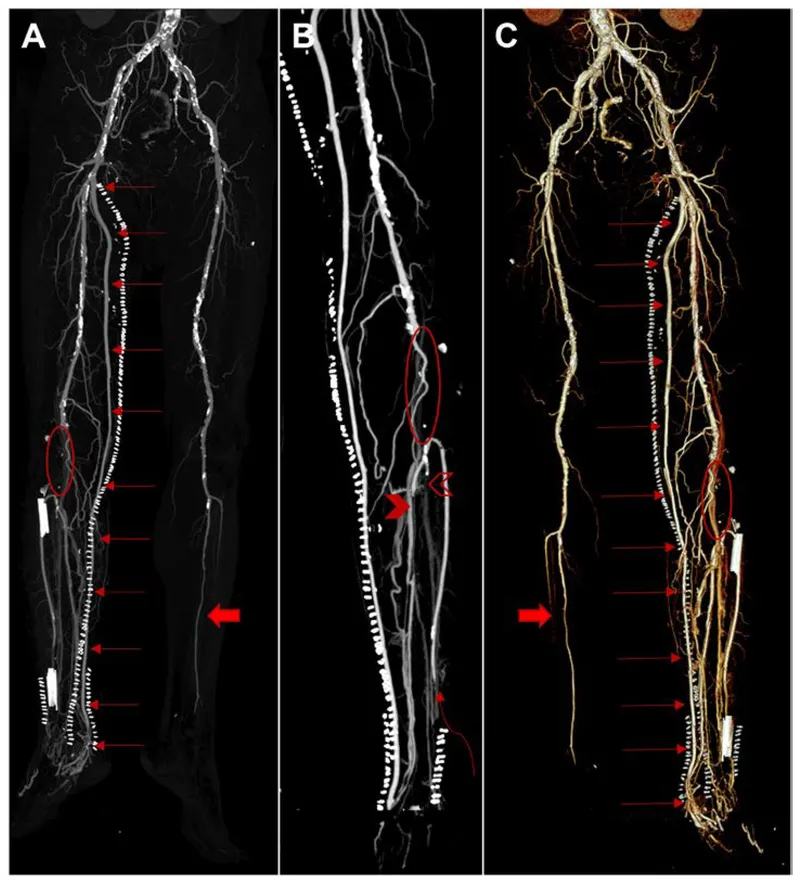

Bypass grafting reroutes blood flow around an arterial blockage using a conduit. Anastomosis connects the graft proximally and distally to the healthy artery.

Principle: Create a new path for blood flow around an occluded or stenotic arterial segment. Choice of conduit is critical for success.